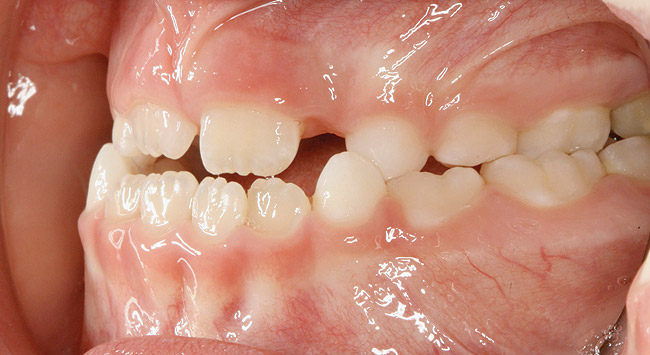

(13.) Seven-year-old brachyfacial child with high body mass index (Case courtesy of James Awbrey, DMD).

Figure 13

(14.) Angle Class III occlusion with constricted maxilla.

Figure 14